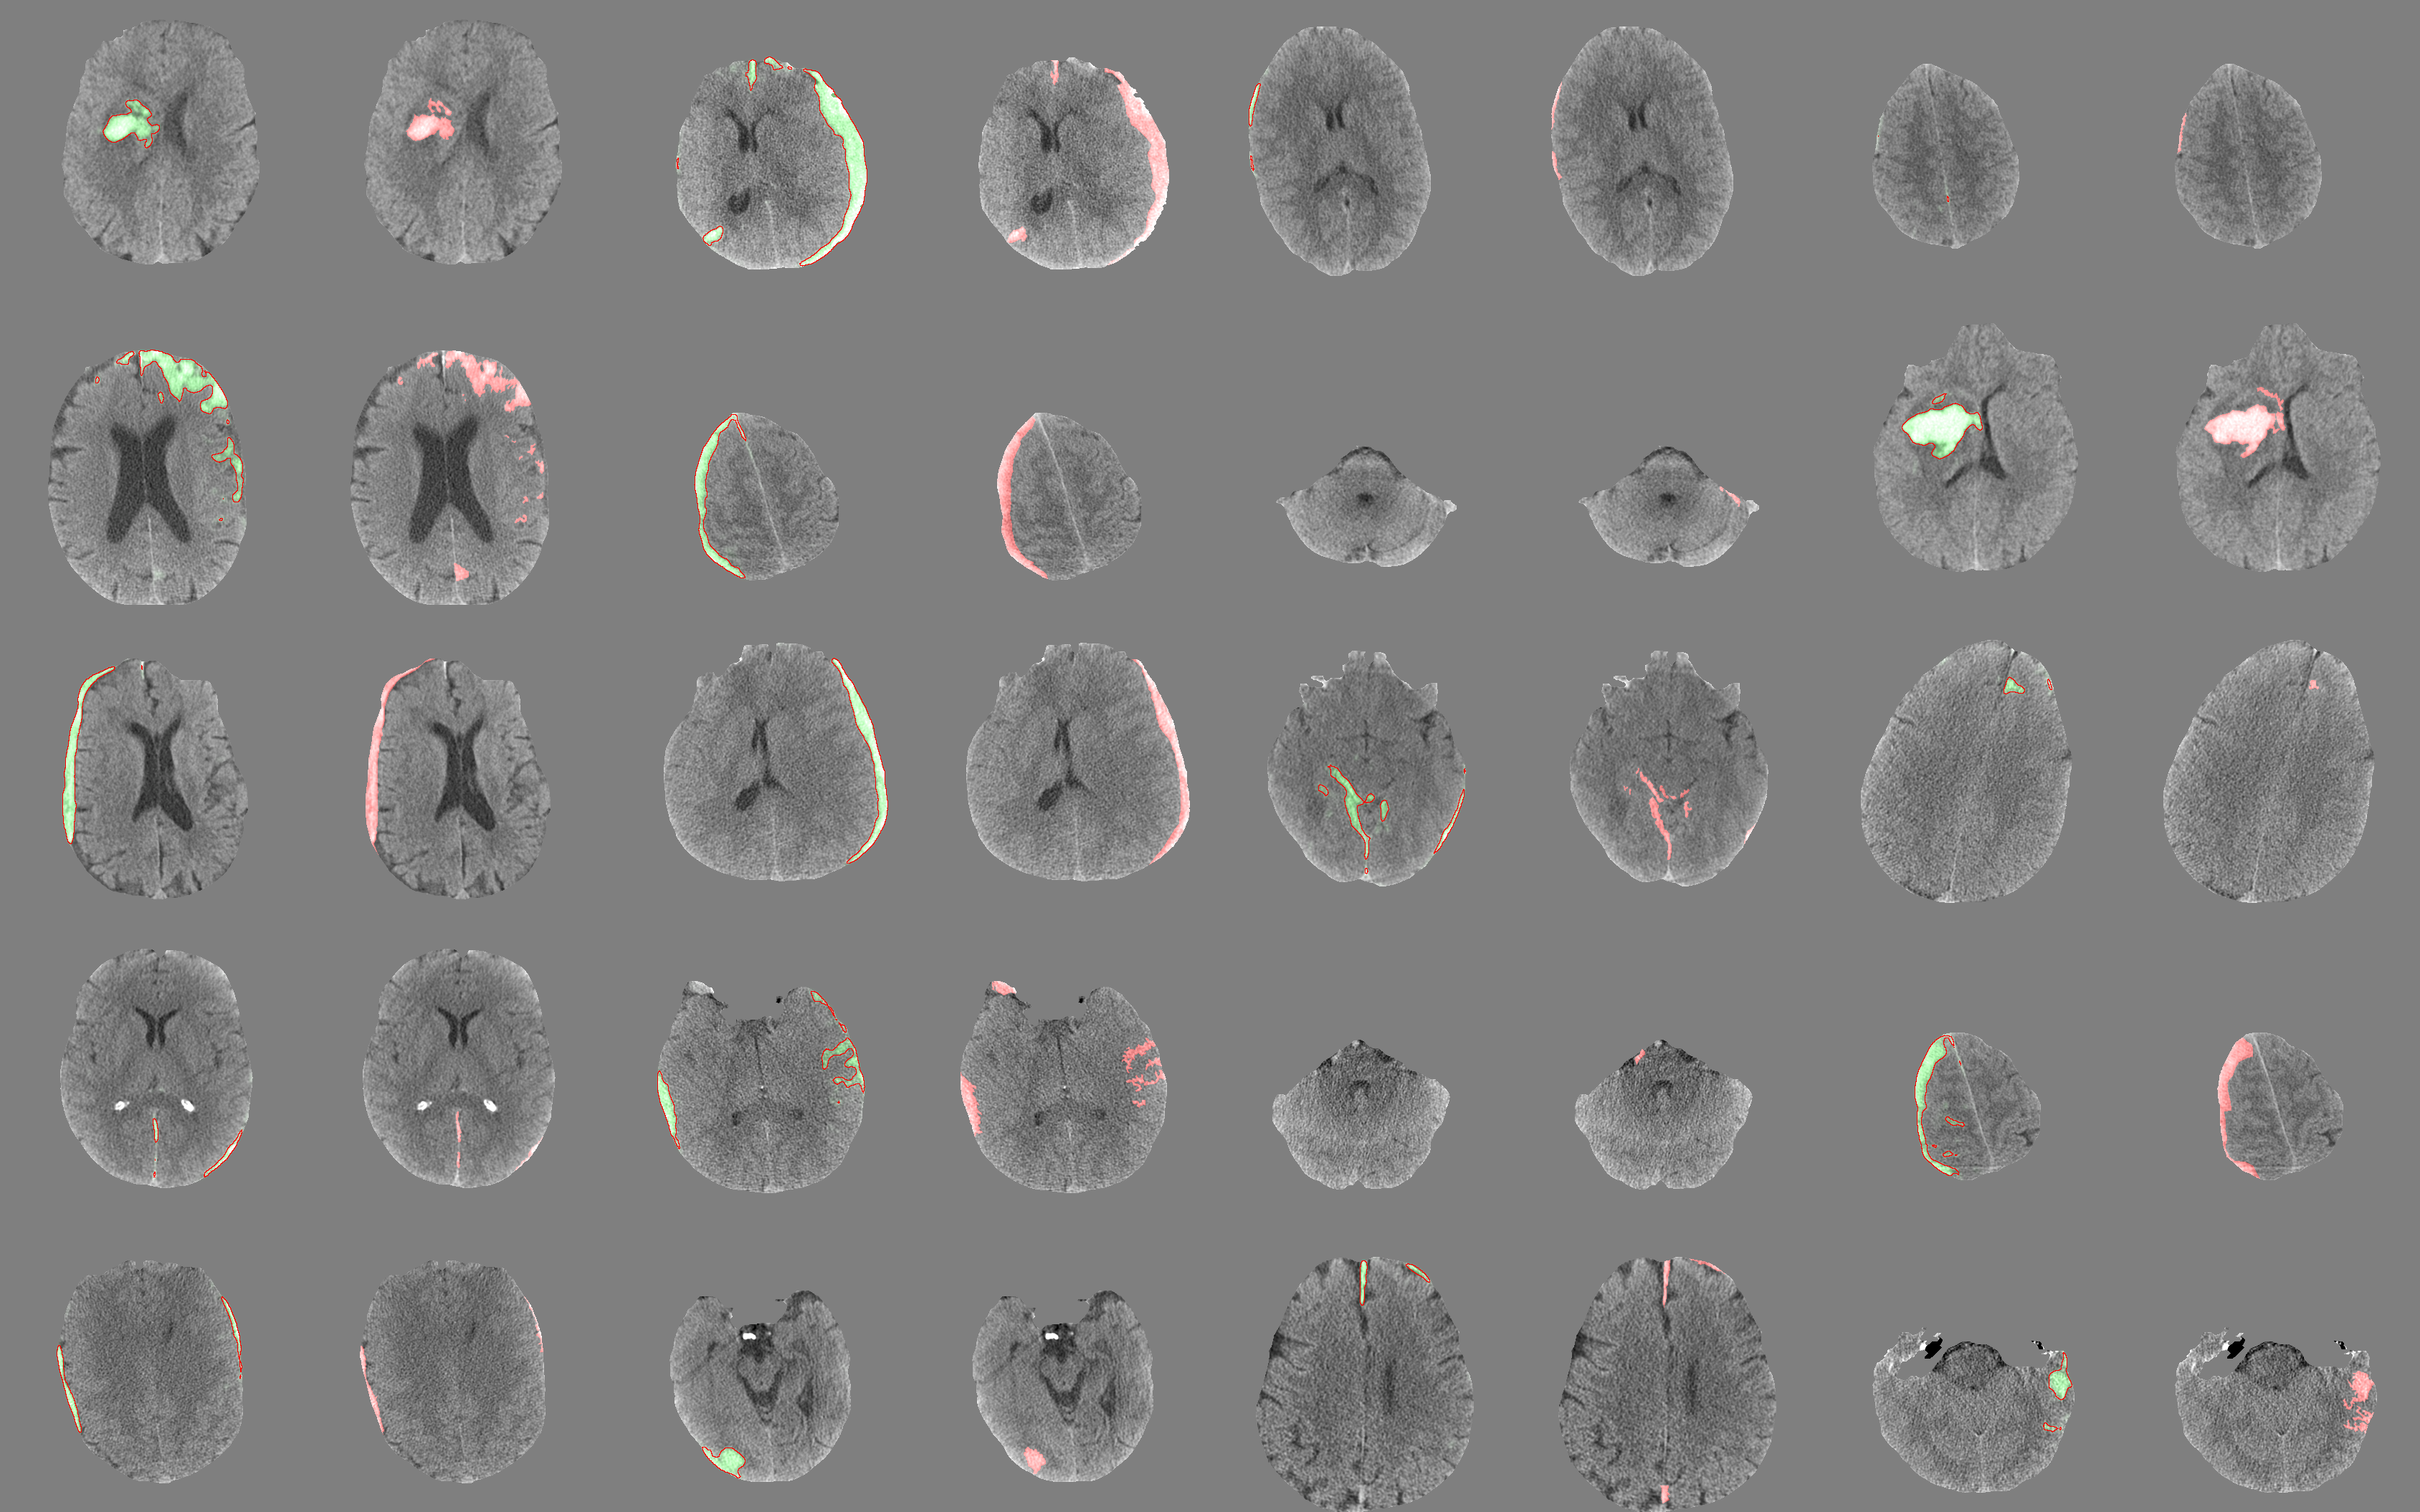

Apart from stack-level evaluation, we evaluate PatchFCN at pixel level because clinicians also want to know the location and volume of the bleeds for disease prognosis. Figure 1 visualizes the outputs of PatchFCN in comparison with the groundtruths. Results are shown on randomly selected positive frames in the retrospective test set.

On the retrospective test set, our model achieves pixelwise Dice score, Jaccard index, and average precision of , , and . In comparison, [4] reports Dice scores of to for a few types of hemorrhages they study. Our groundtruths are annotated pixelwise by senior neuroradiologists who specialize in TBI and include many subtle findings that could be easily missed by inexperienced radiologists. Using both trainval and test data, our 4-fold cross validation Dice score is .